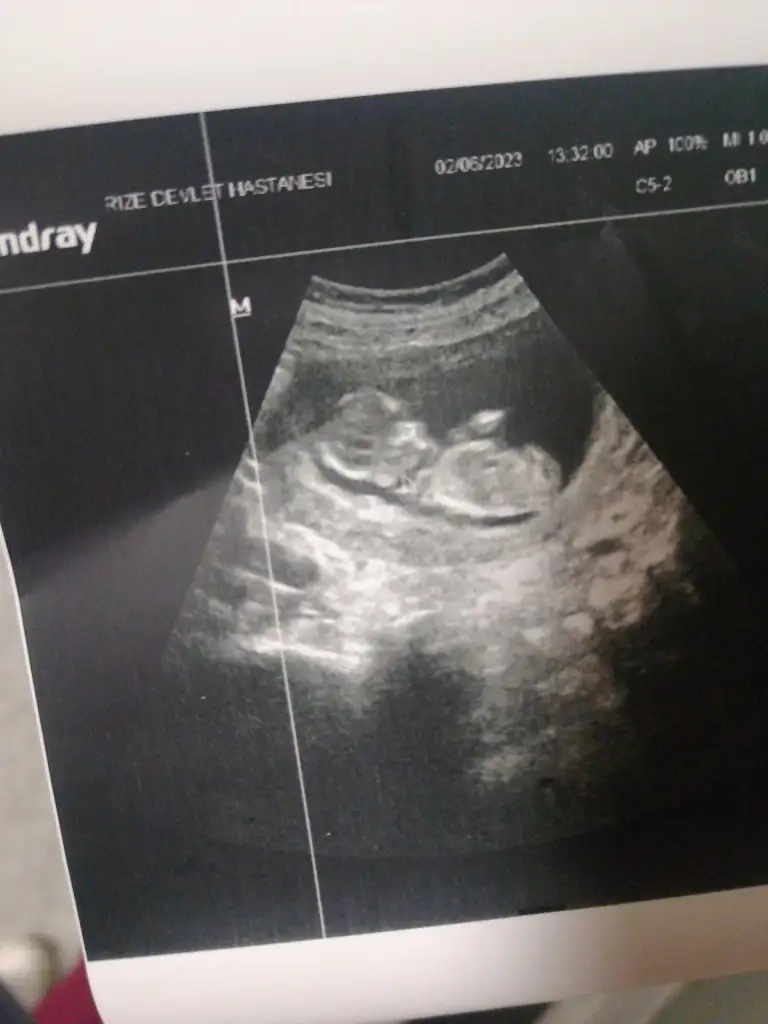

Eklentiler

• IMG-20230602-WA0035.webp

IMG-20230602-WA0035.webp

20,3 KB · Görüntüleme: 45

• IMG-20230602-WA0029.webp

IMG-20230602-WA0029.webp

23,1 KB · Görüntüleme: 57

• IMG-20230602-WA0017.webp

IMG-20230602-WA0017.webp

22,9 KB · Görüntüleme: 67